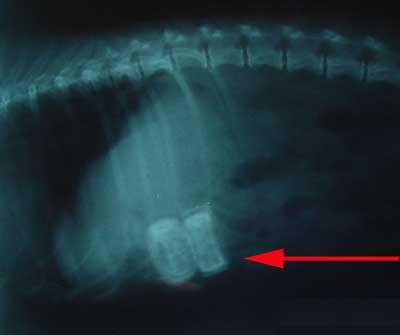

This little dog came in to see the vet because she was unwell. She was admitted for treatment and after thorough examination, an X-ray was taken of her stomach

The dog was opened up (Laparotomy) and these three wheels were found in the small intestine. The dog made a full recovery after the wheels were removed.